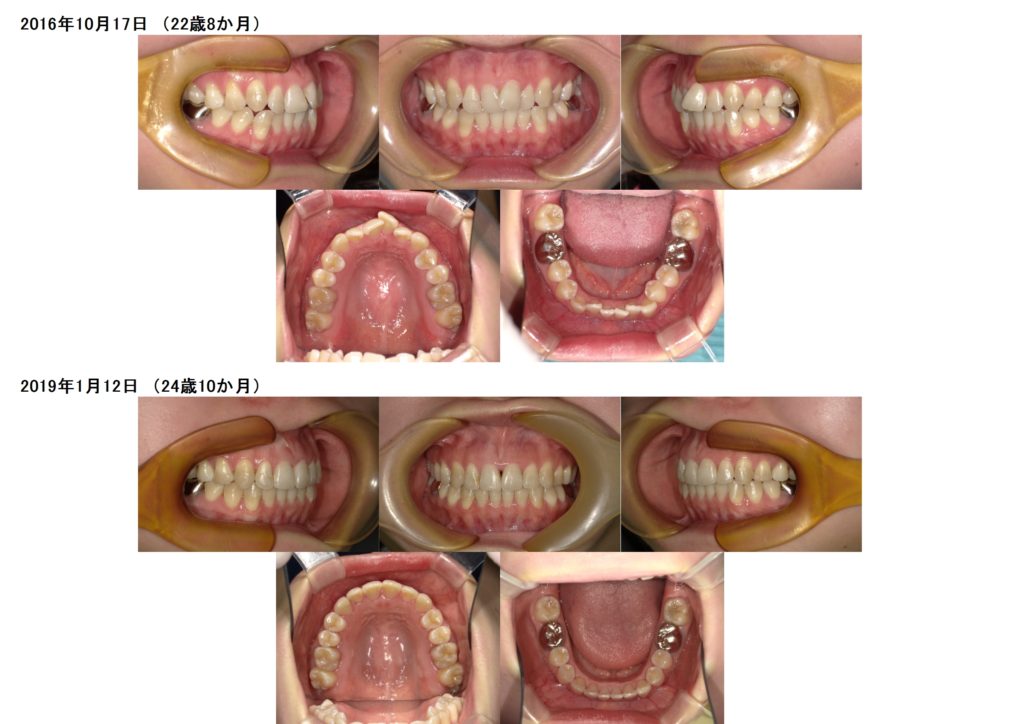

↑上下の写真を見比べると、歯と歯の間にすき間が取れているのが分かります。

奥歯の位置も変わっていたりします。簡単に言うと、顎を広げます。これはお顔が大きくなるわけではないのでご心配なく!!

広げるといっても、その方の骨格に対して理想的な数値にするので、整っている状態になります。

アンカースクリューを使用し、この患者様は遠心移動を行いました。

奥に歯を移動させる治療方法です。

このように、しっかりとスペースが取れたら、インビザラインに移行します。

このように、歯を削らなくても、抜かなくてもとてもキレイな歯並び、かみ合わせを作り上げることが出来ます。